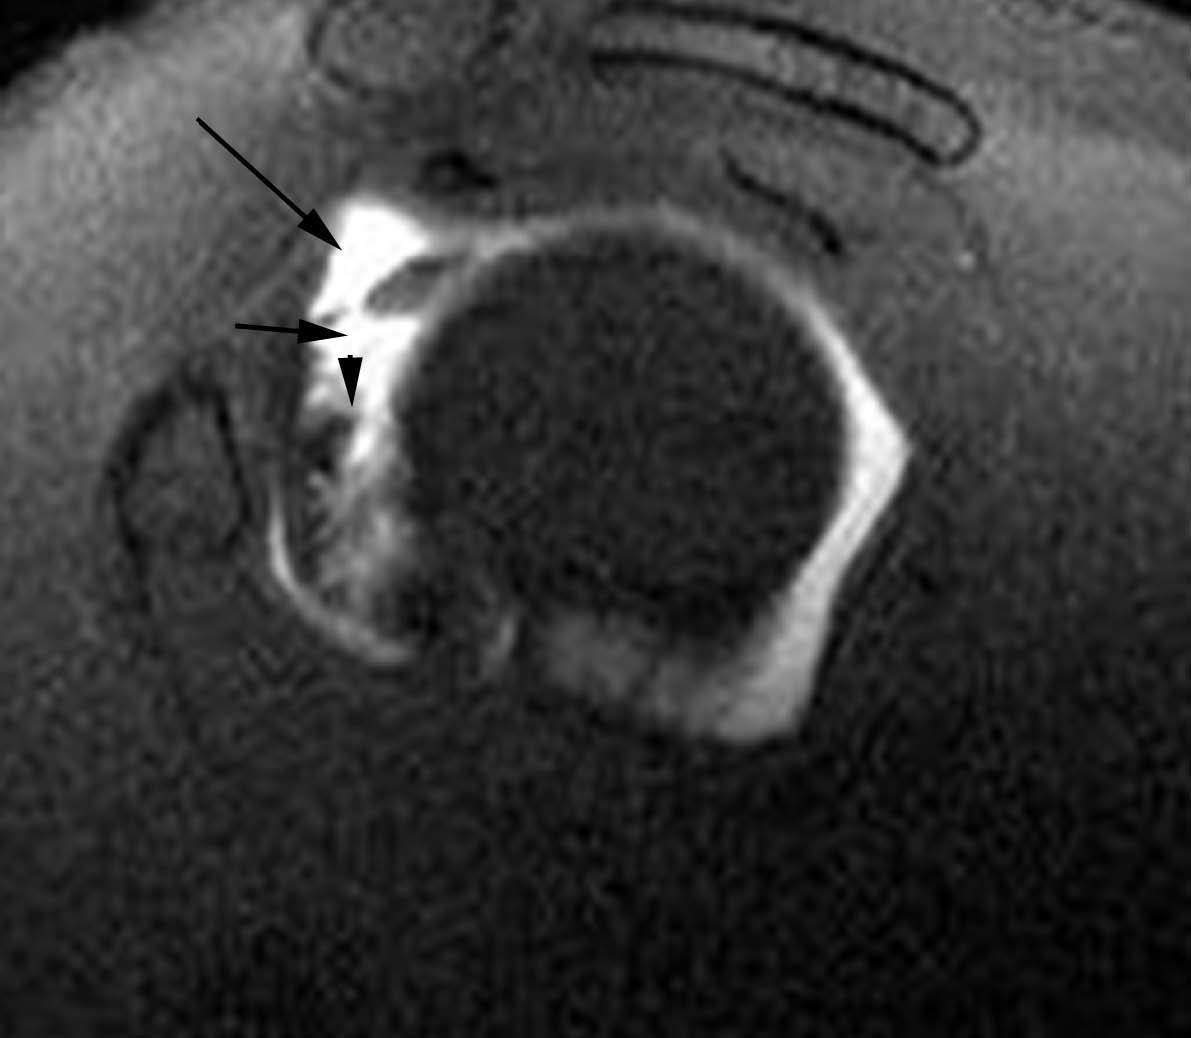

POLPSA (posterior labral periosteal sleeve avulsion)

Esta lesión se asemeja a la ALPSA, pero ocurre en el borde glenoideo posterior. El LG se halla desplazado hacia dentro y por detrás del borde glenoideo posterior. El mecanismo de producción del POLPSA es una dislocación posterior, y por tanto se puede encontrar también un Hill Sachs invertido19 (fig. 14).

. Artrorresonancia axial T1 con supresión grasa donde se observa una rotura del labio glenoideo posterior con desplazamiento posteromedial (flecha). Nótese la situación del labio glenoideo en comparación con una rotura sencilla, no desplazada, que se observa en la figura 13. Obsérvese la presencia de una lesión de Hill-Sachs invertida (cabezas de flecha), en relación con una dislocación posterior con reducción.Lesión de Bennett